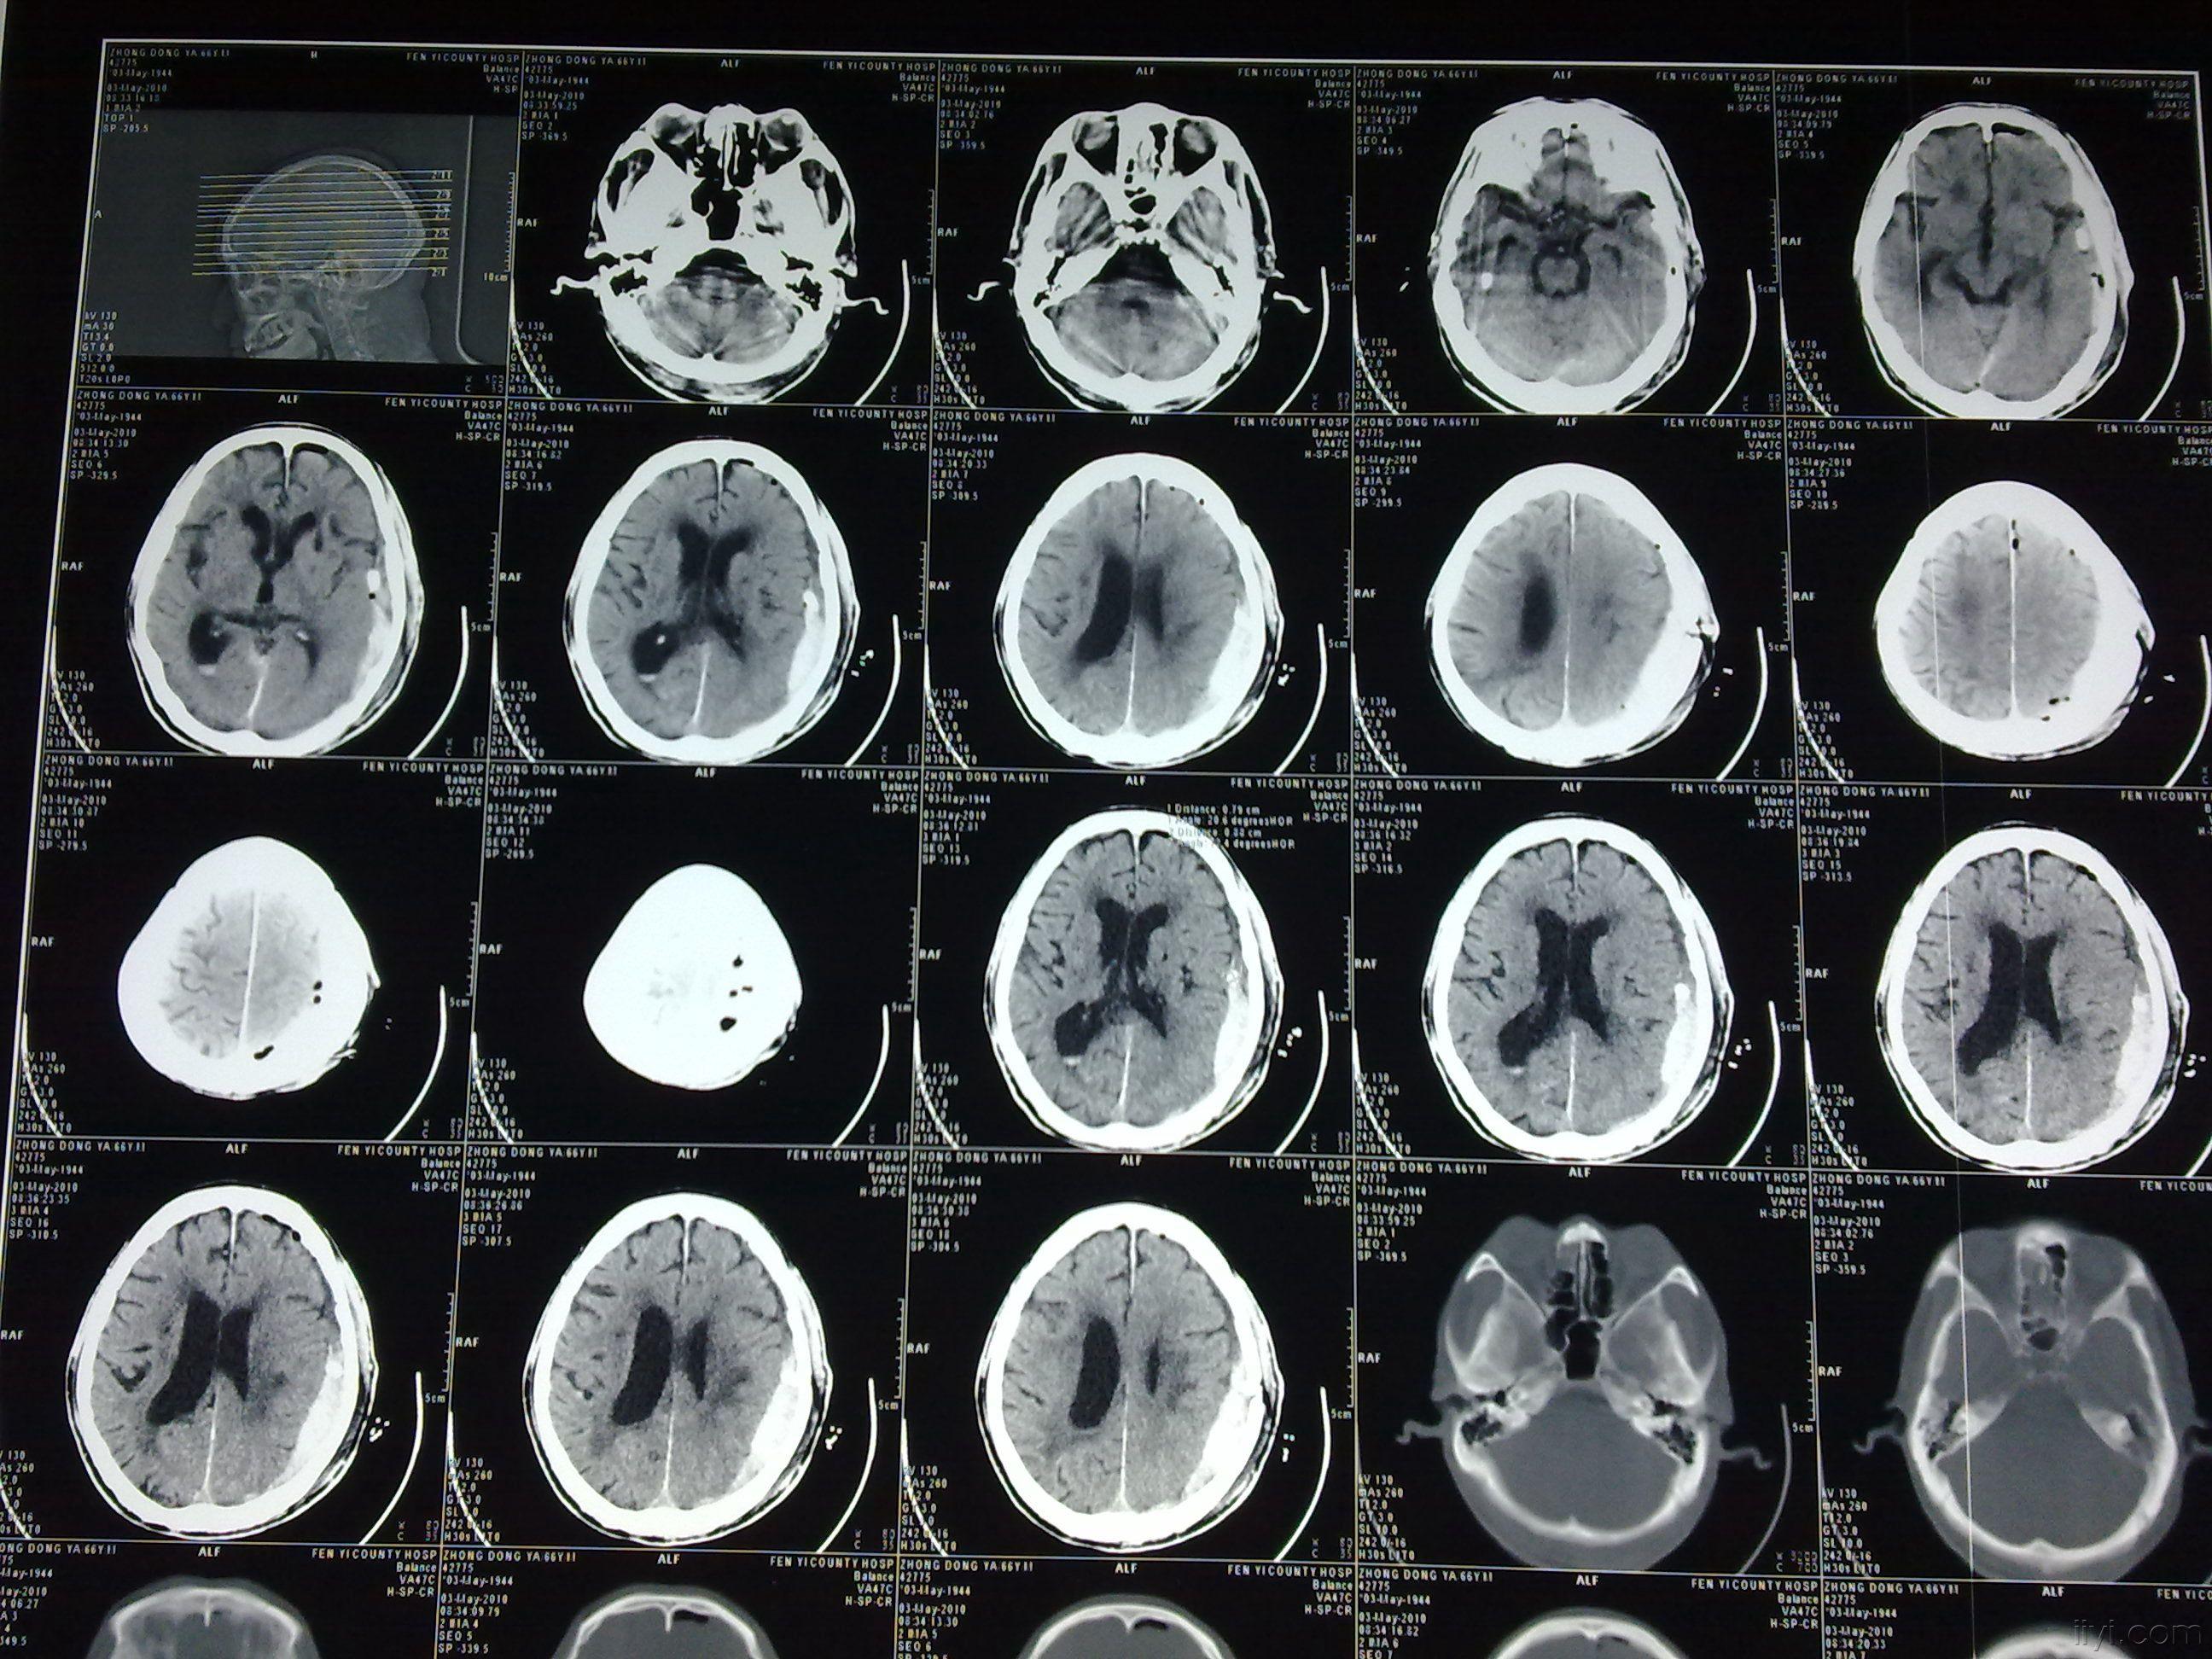

慢性硬膜下血肿再出血 - 神经外科专业讨论版 - 爱爱医医学论坛

又一列硬膜外血肿的病人